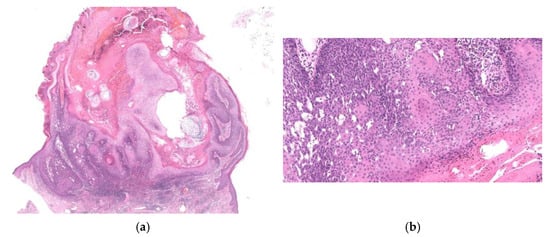

3. Diagnostically Problematic Lesions, KA with a Conventional SCC Component (KASCC)

4. Other Crateriform Tumors

4.2. Other Malignant Neoplasms

4.2.3. Crater Form of Infundibular SCC